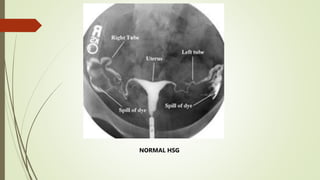

HYSTEROSALPINGOGRAPHY

(HSG)

 In a proved case, HSG is contraindicated for risk of reactivation

 HSG done as a routine work up for investigation of infertility may

reveal the following suggestive features.

HSG FINDINGS IN GENITAL TB

NORMAL HSG